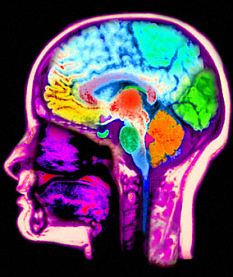

成胶质细胞瘤是人类中最常见和危险的脑肿瘤,其发生恶化的几率极高。这些肿瘤细胞通常扩散很快且分布的边缘界限不清,因此在临床上非常难以进行成像和放疗。最近,科学家们开发了一种新的方法,它能够有效的攻击这些细胞来延缓或阻止它们的恶化。

在最新一期的《Radiology》杂志上,维吉尼亚共和国大学医学院放射物理学和生物学专家Panos Fatouros教授及它的研究小组们宣称,在动物身上,通过一个含有核磁共振成像(MRI)诊断剂的纳米级颗粒可以有效的对这些脑肿瘤进行成像和放射治疗。

这个纳米颗粒中含有钆、非常灵敏的用于成像的MRI造影剂和用于短程治疗的放射性镥177。通过一个简单的混合可以使它能同时有效的进行治疗和成像。